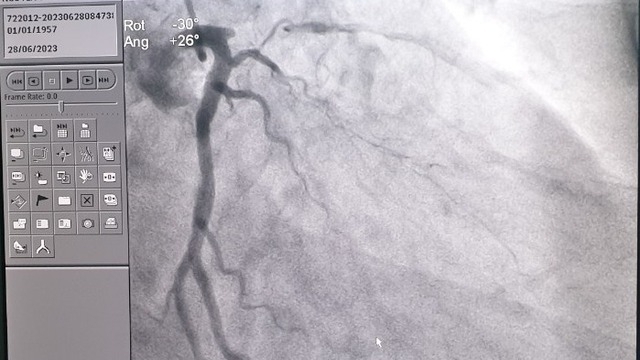

Ca cắt bỏ cánh tay và ca ghép đoạn chi thể được tiến hành đồng thời vào ngày 21/1, tức ngày 27 Tết Canh Tý tại Bệnh viện Trung ương Quân đội 108. Giáo sư, Tiến sĩ khoa học Nguyễn Thế Hoàng, Phó Giám đốc Bệnh viện cho biết, ekip thực hiện ca ghép đều là y, bác sĩ Bệnh viện Trung ương Quân đội 108.

“Ca ghép diễn ra khoảng 8 tiếng đồng hồ, từ 10h sáng đến hơn 6 giờ tối. Để nối phần chi thể từ 1/3 dưới cẳng tay đến bàn tay, chúng tôi phải nối tới 36 cơ và có 2 xương, cùng với cấu trúc xương, màng xương, tủy xương. Riêng bàn tay có đến gần 40 cái xương. Về sau những phần được nối này sẽ liền hết với nhau, tạo thành một khối”, ông Nguyễn Thế Hoàng cho biết.

Sau ca ghép, tất cả các cấu trúc giải phẫu đã phục hồi, tức là đoạn chi thể từ 1/3 cẳng tay đến bàn tay trái sau khi được ghép vào cơ thể anh Phạm Văn Vương đã được tưới máu đầy đủ giống như bên tay phải. Đến nay, chỉ hơn 1 tháng sau ca ghép, anh Vương đã có thể sử dụng bàn tay trái để nắm một số đồ vật và các tín hiệu hiện nay cho thấy khả năng hồi phục là trên 50%.